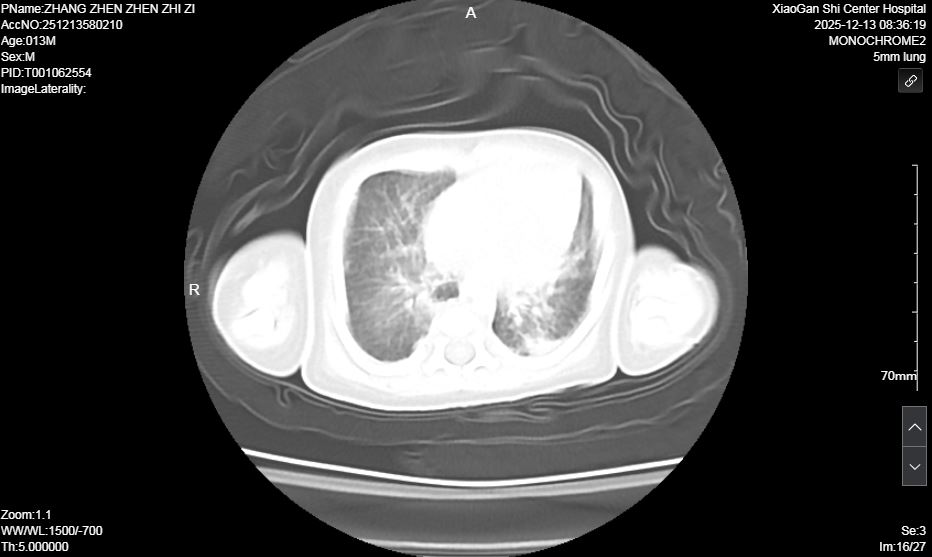

患兒入院后,NICU團隊立即啟動危重新生兒搶救預案。經快速檢查,初步診斷為宮內感染所致的足月兒急性呼吸窘迫綜合征(ARDS),該疾病極易合并肺高壓、氣胸、肺出血、呼吸衰竭等嚴重并發(fā)癥,屬于新生兒急危重癥,救治難度極大。團隊立即按新生兒ARDS診療規(guī)范進行氣管內給予肺表面活性物質,循環(huán)支持,抗感染、持續(xù)機械通氣、營養(yǎng)支持等對癥治療。然而,由于原發(fā)疾病嚴重,患兒經歷7天機械通氣后,病情出現反復,肺部影像學顯示雙肺實變明顯,脫氧撤機困難。

術前肺部超聲及CT均提示雙肺實變明顯